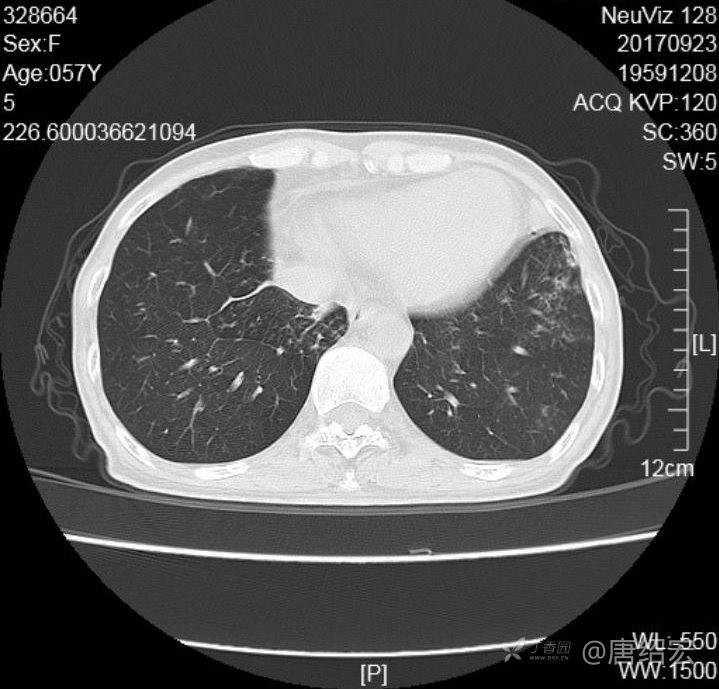

女,57岁,

主诉:发热、咳嗽、咯黄痰,胸闷3天入院。

铜绿假单胞菌性肺炎 (12)

铜绿假单胞菌感染 (20)